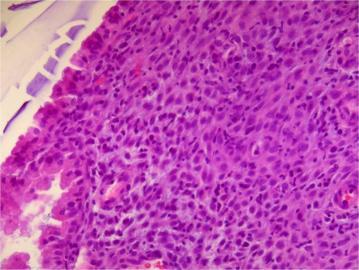

Seminoma - homogenous form, macroscopically heomogenous tumor, seminoma cells - prominnent nucleoli, cytoplasm clearing (glycogen)

tumor infiltrating lymphocytes